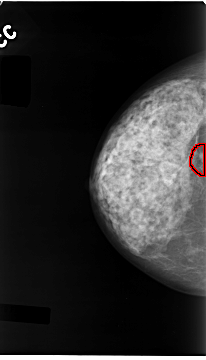

C_0052_1.RIGHT_MLO

RIGHT_CC LINES 4680 PIXELS_PER_LINE 2672 BITS_PER_PIXEL 12 RESOLUTION 50 OVERLAY

FILE: C_0052_1.RIGHT_CC.OVERLAY

TOTAL_ABNORMALITIES 1

ABNORMALITY 1

LESION_TYPE MASS SHAPE LOBULATED MARGINS MICROLOBULATED

ASSESSMENT 4

SUBTLETY 1

PATHOLOGY MALIGNANT

TOTAL_OUTLINES 1

BOUNDARY